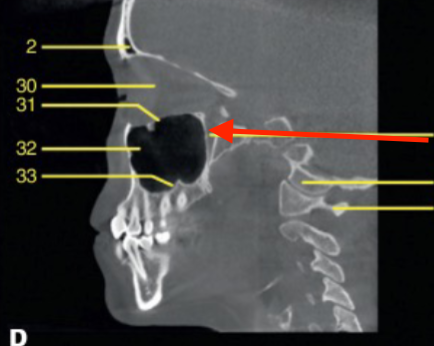

sagittal

what plane is this

sella turcica

identify the structure

hard palate

mandibular condyle